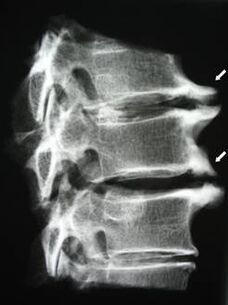

In the initial stages, osteochondrosis is detected using MRI.Later, pathology can be diagnosed using radiography.On radiographs of the cervical spine, a decrease in the distance between the vertebrae, pathological changes in the facet joints, and osteophytosis become noticeable.

| Cervical osteochondrosis | The appearance of pathological changes in one or more spinal motion segments.Impaired spinal mobility, development of myofascial pain syndromes and pinching of spinal roots | Pain, paresthesia and motor disturbances in the cervical region, which spread to the back of the head and upper limbs.Detection of characteristic changes in the spine on MRI and radiographs (osteophytes, decreased distance between vertebrae, signs of damage to intervertebral joints) |